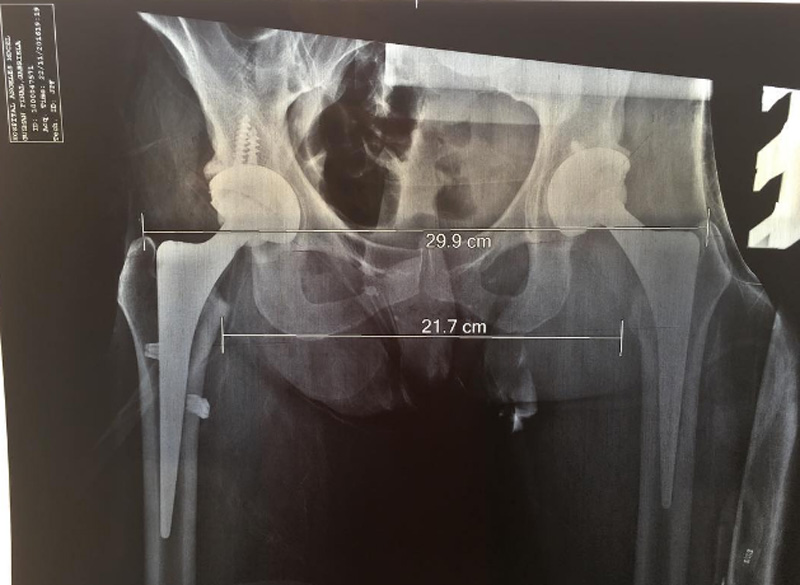

CIUDAD DE MÉXICO.- La intérprete de “Un día de suerte”, quien fue sometida a una operación de cadera, compartió en sus redes sociales una radiografía donde se muestran las prótesis de titanio que le fueron implantadas.